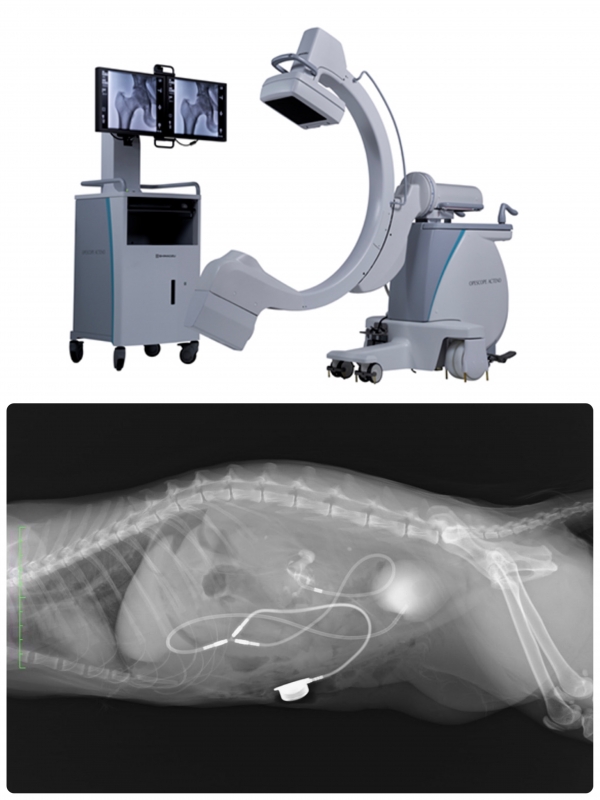

cアーム導入しました。

手術中に身体内部の骨、臓器、血管などを観察するためのX線透視診断装置です。

これが導入されたことにより、より正確な整形外科手術やSUBシステムを的確に行うことが可能となります。